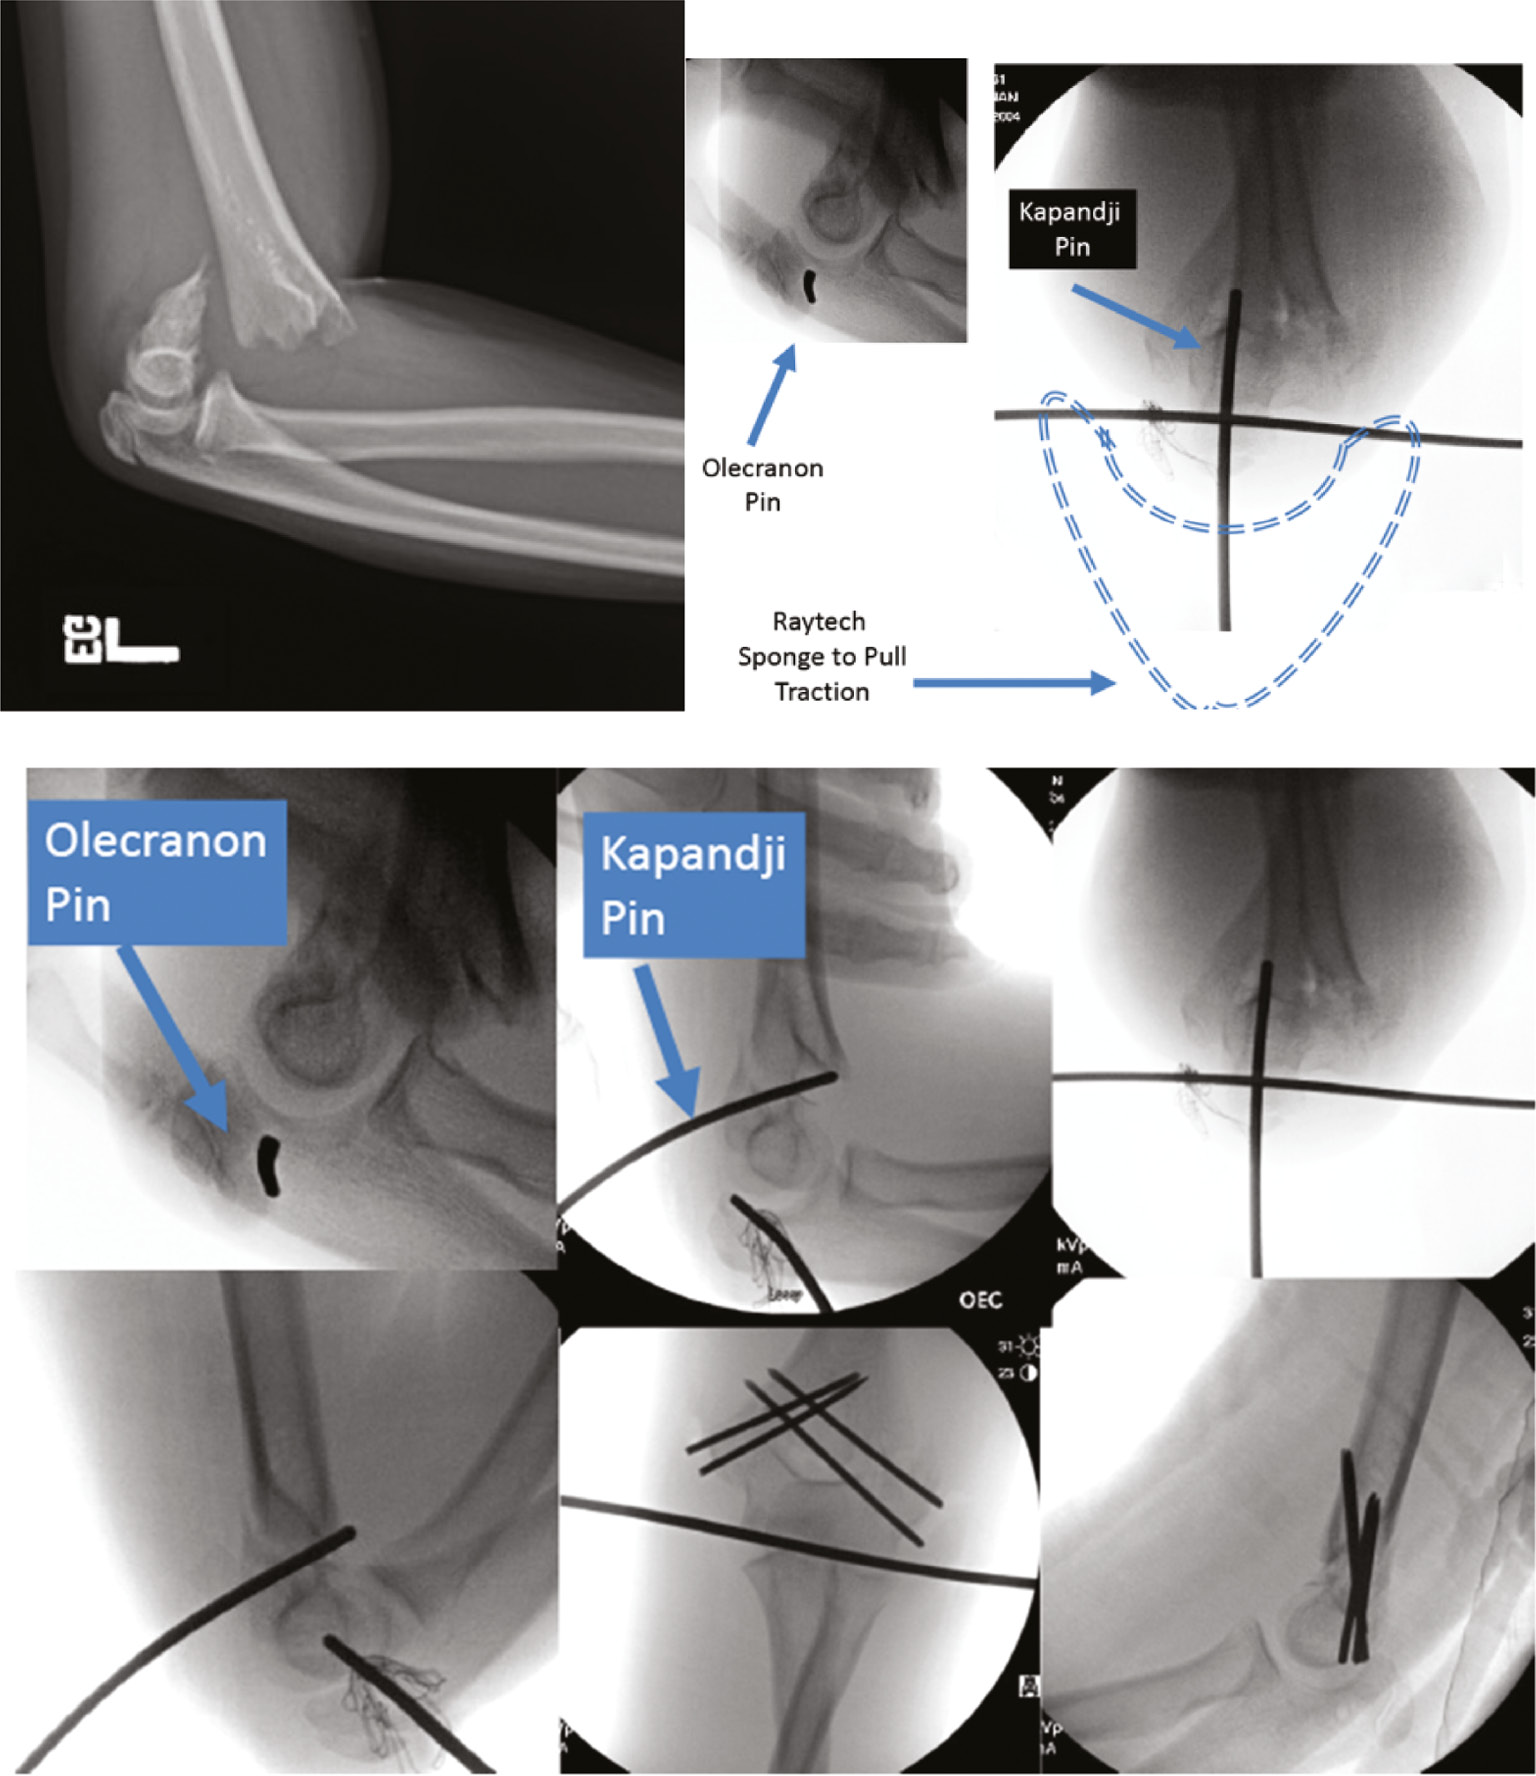

Pins can also be used to effectuate a reduction via the Kapandji method or with temporary intraoperative olecranon pin traction (Figures 4 and 5).

Figure 4. This 9-year-old with a supracondylar humerus fracture was reduced with a posteriorly placed K-wire as a joy-stick. The medial pin was placed through a small incision to avoid ulnar nerve injury.

Figure 5. This 12-year-old with a supracondylar humerus fracture required a temporarily placed olecranon pin to gain traction while a Kapandji wire leveraged the fracture to a reduced position. Medial pins were placed through an incision and the pins were cut off below the skin. Adolescent fractures often require more than 3 weeks of pin fixation and are at increased risk of infection. These pins were buried to prevent pin tract infection and possible joint sepsis.